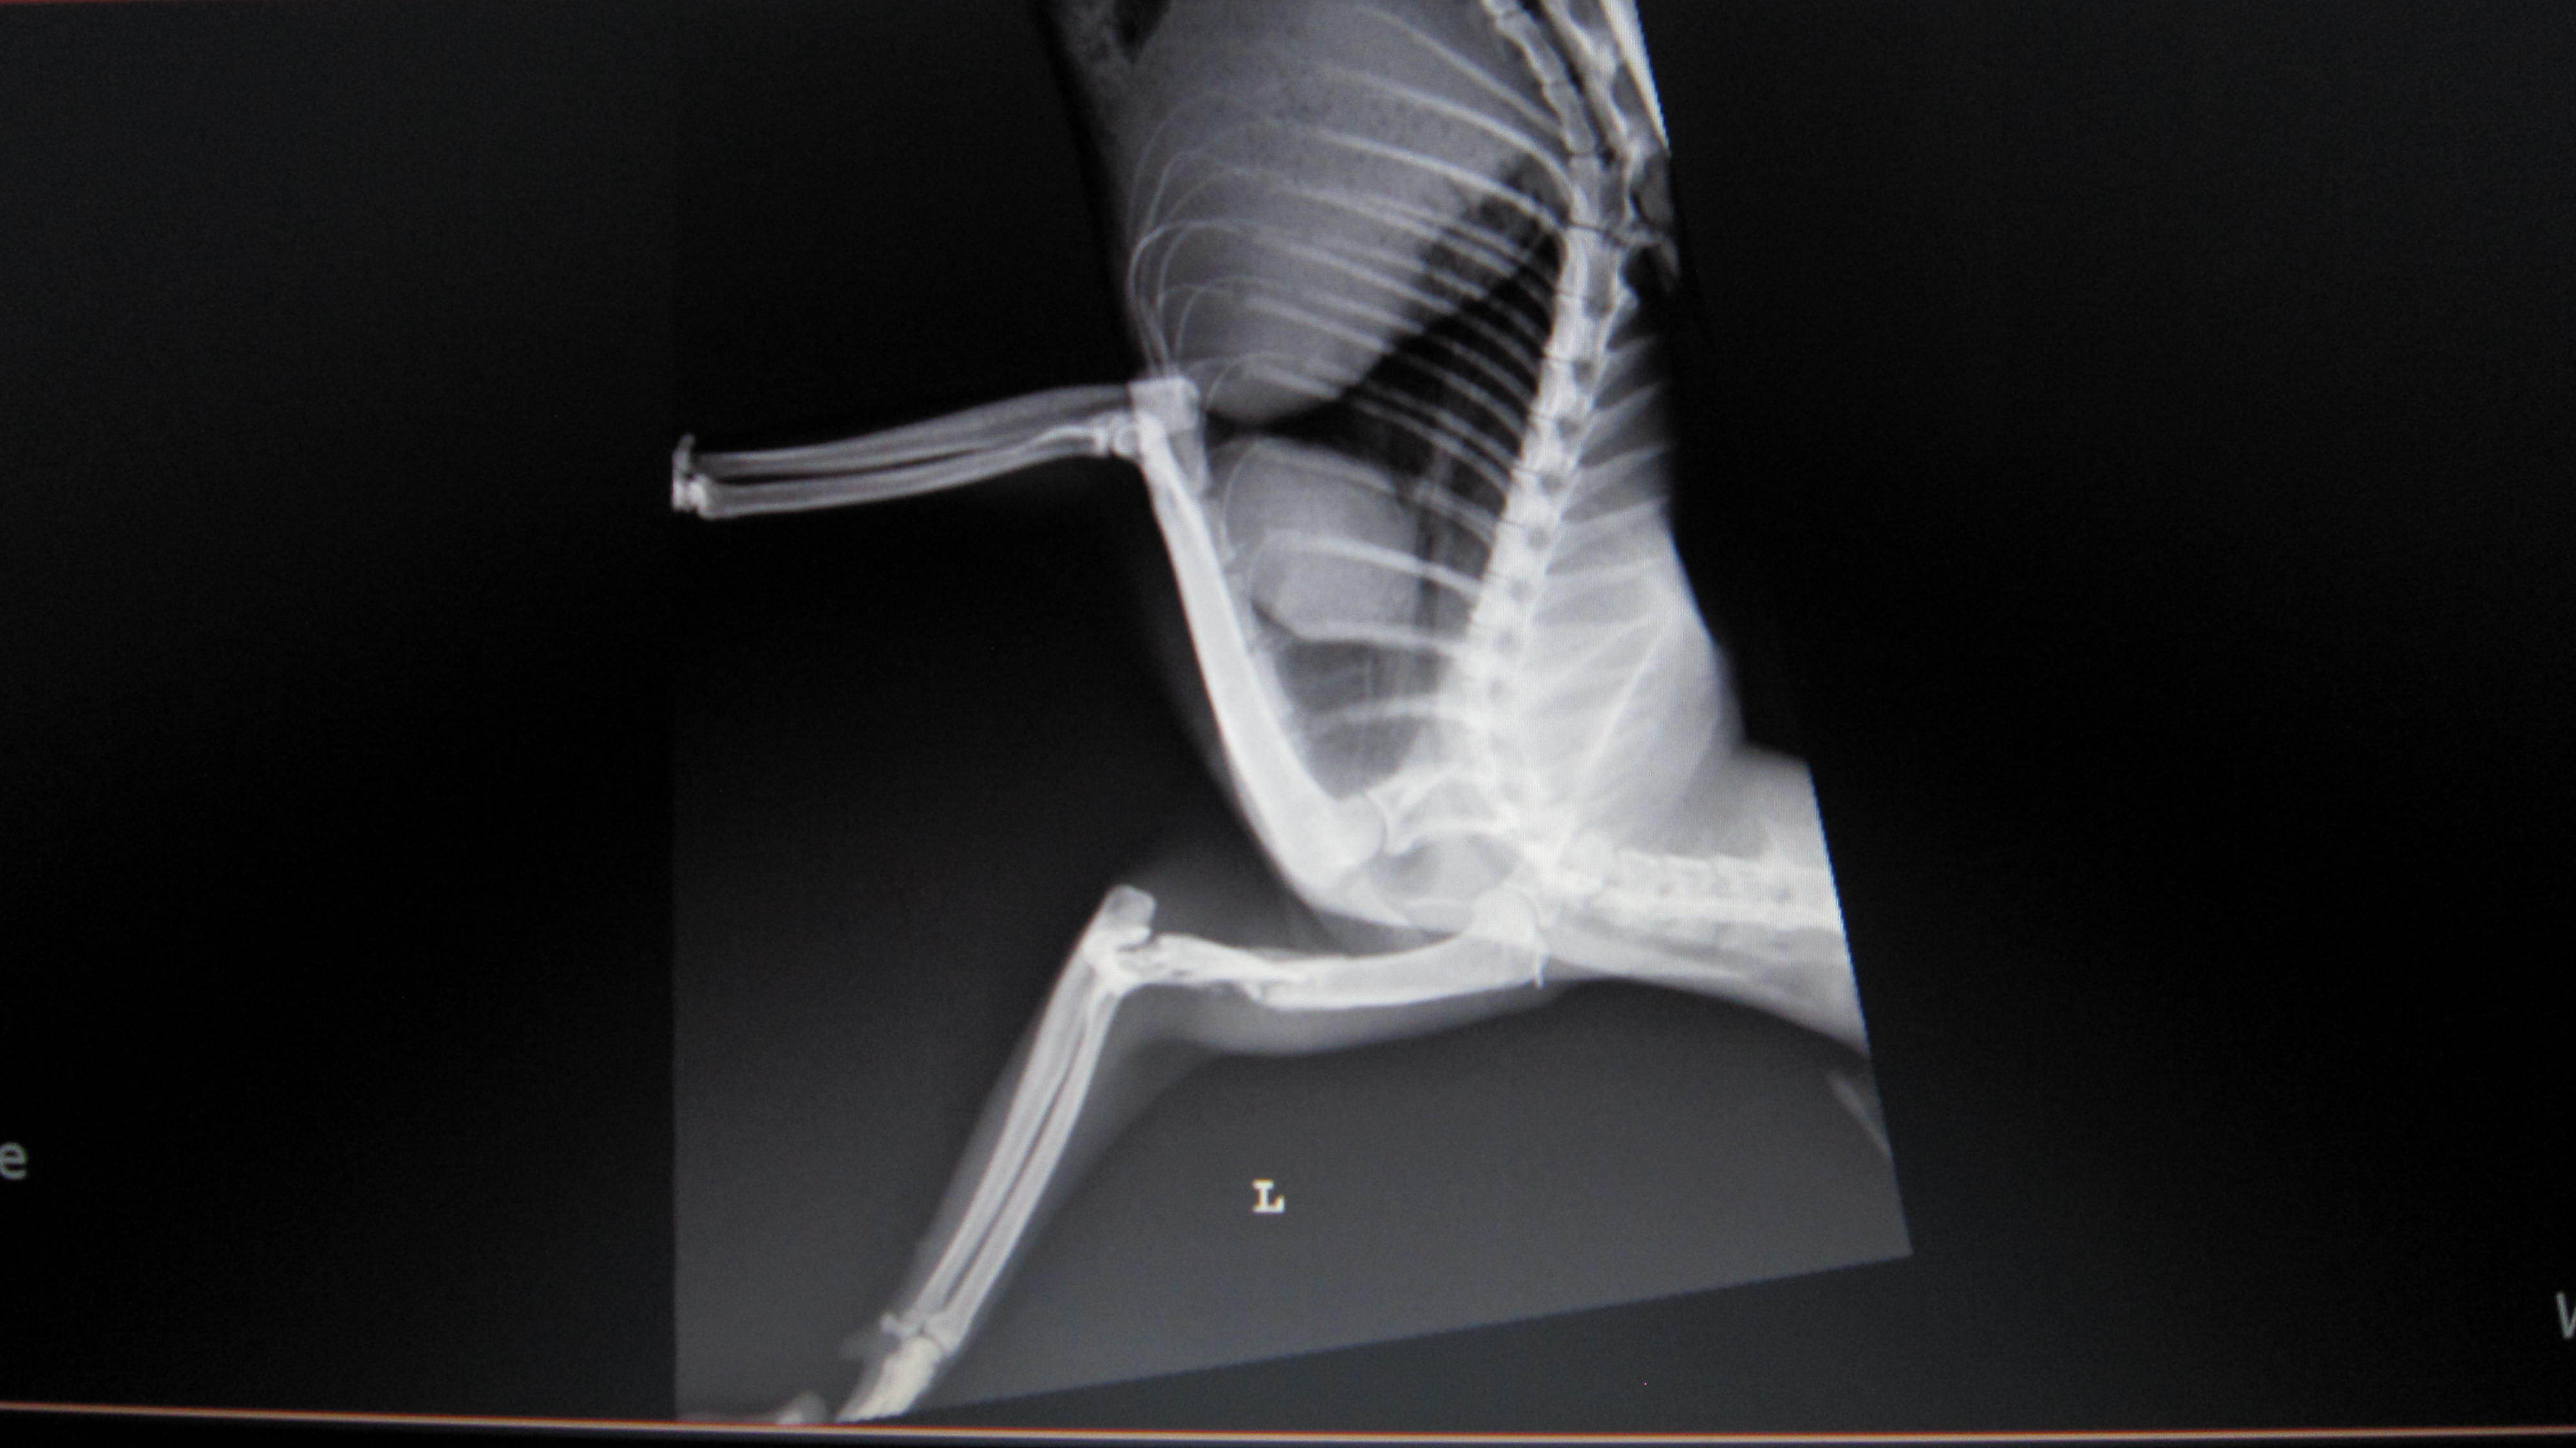

主題: 八德市大湳市場倒在路旁的斷腿貓 (第二次醫助通報) 申請者姓名: 李明明 花色: 申請日期: 2013-06-09 22:30:55 申請者部落格: 申請者臉書網址: 所在縣市/合作醫院: 台北市/長青動物醫院 治療費用: 27160元 需求人數: 29人 已結案 (2013-08-06 14:00:31) 報名人員: 白婷(已付款)、Forest(已付款)、Alison Lee(已付款)、euca(已付款)、言則(已付款)、miraai(已付款)、周小蕾(已付款)、sfeng(已付款)、vivian(已付款)、Rachel Chen x2(已付款)、宋小璉 x2(已付款)、chiawei(已付款)、suxiwen(已付款)、Ping Hussard(已付款)、PS Yeh x2(已付款)、Vinnie Hsu(已付款)、Iris Hsu、Iris Hsu(已付款)、nicole chen(已付款)、Sunny Chen、Sunny Chen(已付款)、蘇小優(已付款)、林嘉南(已付款)、Nonie Huang(已付款)、Ariel Yu-Ting Tu、Kyra Chu(已付款)、林艾蓁(已付款)、chiawei(已付款)、JASON(已付款)、 候補人員: 動物病情說明: 5/11白蛋白已由1.9上升至2.3,食慾佳;每天仍須早晚兩次左後腳背傷口清創,並配合抗生素治療,促進傷口癒合,醫院將視傷口癒合情形調整清創次數。腹水部分先以補充營養與熱量,觀察白蛋白指數回升情形,決定後續治療。另,醫生告知,觀察馬太昨天 (5/12) 有癲癇發作一次,目前繼續觀察中。左前肢雖骨折但已能稍微站立,恢復情形較佳;後肢因關節韌帶受損、腳背傷口清創&肌肉腫脹,恢復較緩慢。 動物近況說明: 斷腿貓(馬太) 6/2 出院,醫療費用合計27,160元 , 已帶回桃園就近照顧,限制活動並定時每日傷口換藥,穩定復原中。